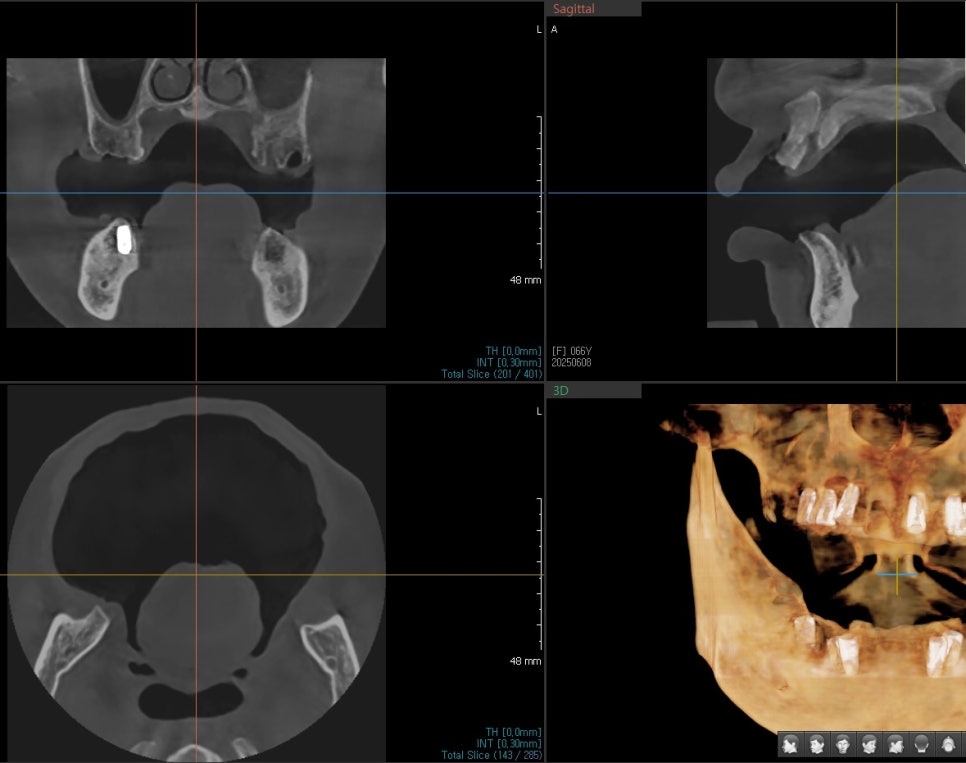

정밀 진단 및 치료 계획

서울오브치과병원에서는 상·하악 전체를

3D CT로 정밀 분석한 뒤 치료 계획을 수립했습니다.

상·하악 총 13개 임플란트 식립

부족한 뼈는 동종골로 이식

어금니 중심의 교합 설계

최종 보철은 원내 기공소에서 맞춤 제작